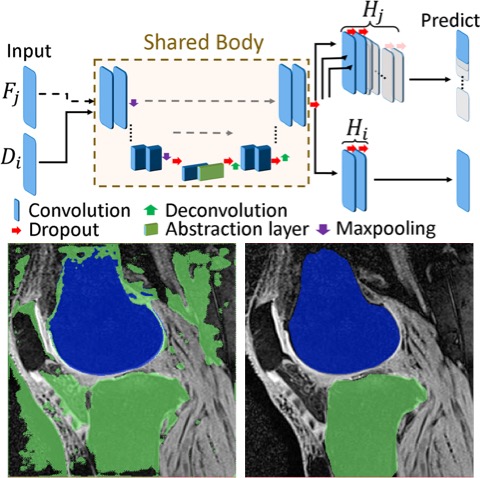

[2019] Firat Ozdemir and Orcun Goksel:

"Extending pretrained segmentation networks with additional anatomical structures",

Int J Computer Assisted Radiology and Surgery 14(7):1187-1195, Jul 2019.

[2019] Firat Ozdemir and Orcun Goksel:

"Extending pretrained segmentation networks with additional anatomical structures",

Int J Computer Assisted Radiology and Surgery 14(7):1187-1195, Jul 2019.

[2021] Firat Ozdemir, Zixuan Peng, Philipp Fuernstahl, Christine Tanner, and Orcun Goksel:

"Active Learning for Segmentation Based on Bayesian Sample Queries",

Knowledge-Based Systems 214(106531):1-9, Feb 2021.

[2021] Firat Ozdemir, Zixuan Peng, Philipp Fuernstahl, Christine Tanner, and Orcun Goksel:

"Active Learning for Segmentation Based on Bayesian Sample Queries",

Knowledge-Based Systems 214(106531):1-9, Feb 2021.